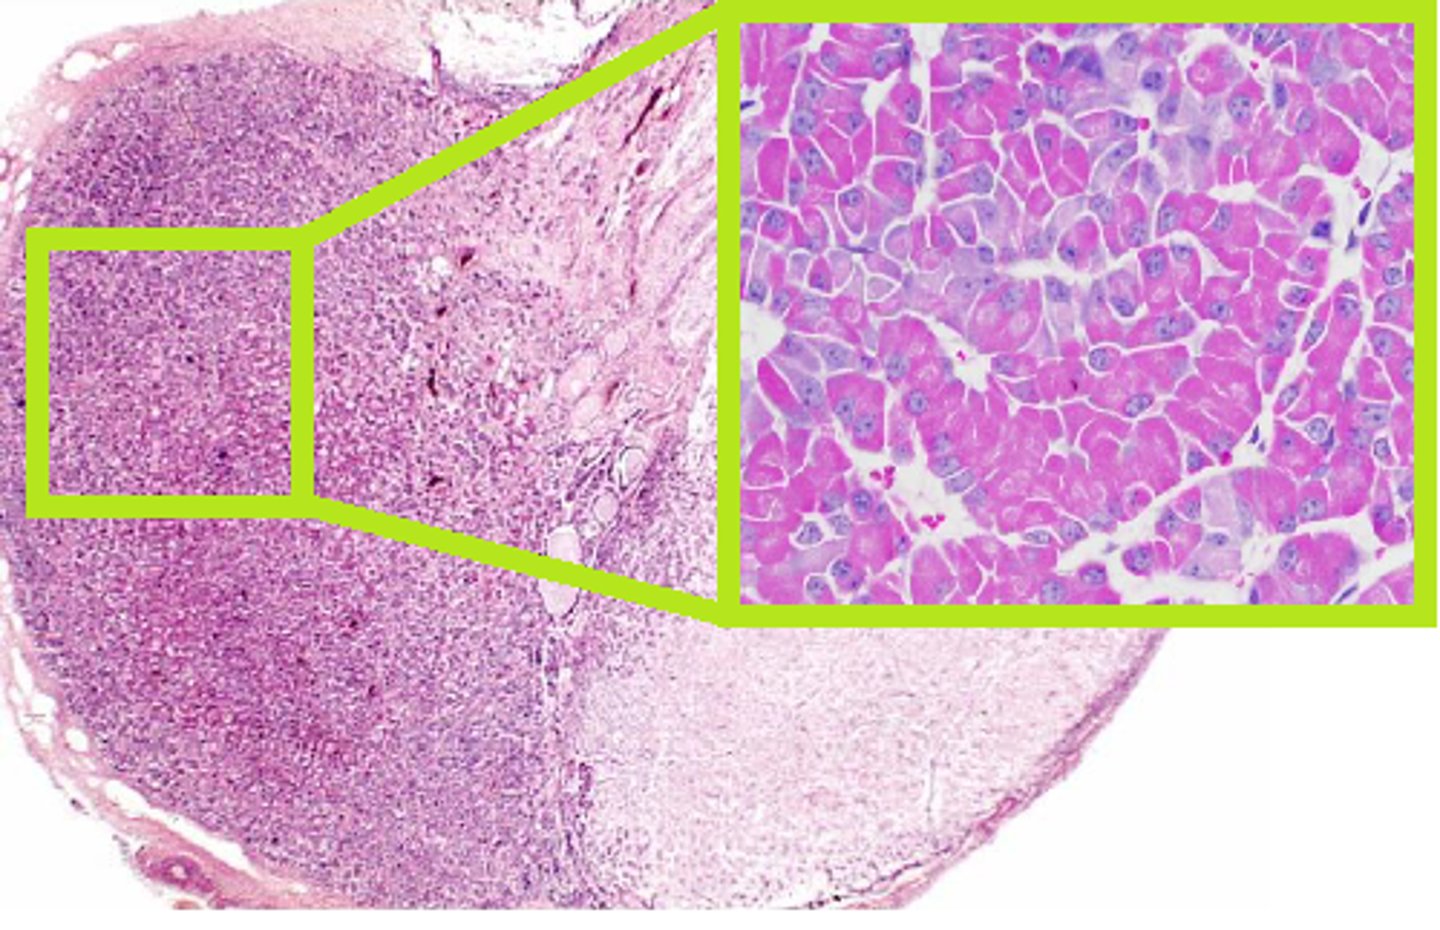

Pituitary gland

Acidophils Cells of the anterior Pituitary Gland

Secrete growth hormone, prolactin

Basophils cells of the anterior pituitary gland

Secrete FSH LH and TSH

Pituicyte cells of the posterior pituitary gland

Pancreas cells cross section

Consists of exocrine cells and endocrine cells

Endocrine cells islet of langerhans of the pancreas

Secretes: insulin, glucagon, somatostatin

Exocrine Tissue of pancreas

A

Synthesizes and secretes digestive proenzymes and enzymes

Adrenal Gland cross section

Adrenal Cortex

Thick light pink circle

Adrenal medulla

3, inside of gland